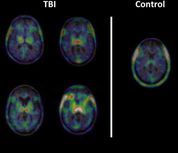

Positron Emission Tomography (PET)

The Siemens Biograph 6 PET/CT scanner features 6 slice CT, a multi-detector ring system and 3D reconstruction. An Allogg Automated Blood Sampling System (ABSS) is available for those studies which require arterial blood sampling; there is also an adjacent tissue/blood processing lab with dual-HPLC/radioactivity detectors for tracer metabolite analysis.